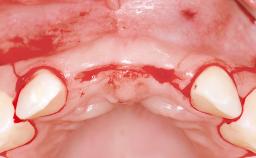

A 45-year-old woman was referred for management of an infection associated with two implant-supported crowns replacing the maxillary central incisors. Two tissue-level implants had been placed and restored with cemented single metal-ceramic crowns in those sites 4 years previously. The patient presented with a draining sinus (i.e. a pathological duct from an abscess cavity to a surface) 3 mm from the midfacial peri-implant mucosal margin of the maxillary right implant crown. She was in good general health, did not smoke, showed a good oral hygiene status, and had no history of periodontal disease. The implants were well positioned. While the patient was very satisfied with the appearance of her crowns, she had noted that the peri-implant soft tissue had receded since their insertion and was concerned about the possibility of further recession.